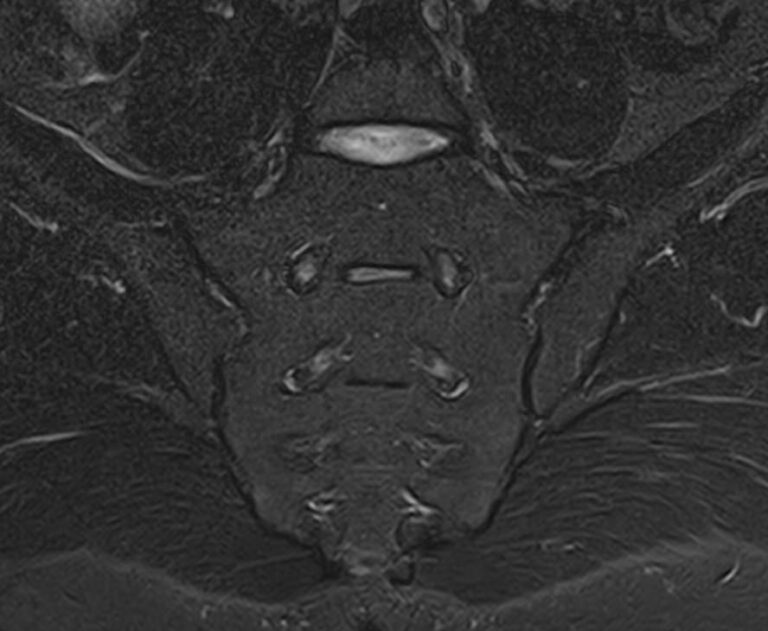

Наиболее точным и эффективным способом диагностики причин появления болей в нижней части спины является МРТ. С помощью данного метода можно оценить состояние всех анатомических структур позвоночного столба на исследуемом уровне, диагностировать поражение позвоночника на начальной стадии, когда другие методы не дают результатов. Такой патологией, в частности, является сакроилеит (воспаление крестцово-подвздошного сочленения), который часто становится причиной анкилоза (сращения) или нестабильности (патологической подвижности) сустава. Выявление сакроилеита на ранней стадии значительно улучшает прогноз в плане лечения и профилактики осложнений.

В клинике «Доступная медицина» диагностика патологии нижней части спины осуществляется на высокотехнологичном оборудовании – новейшем высокопольном томографе TOSHIBA VANTAGE TITAN 1,5 Тесла, который обеспечивает высочайшее качество изображений, точность и достоверность полученных данных. Магнитно-резонансная томография осуществляется без применения ионизирующего излучения, поэтому является безопасным методом обследования и может применяться неоднократно по мере необходимости.

Что можно диагностировать при проведении МРТ пояснично-крестцового отдела позвоночника + МРТ крестцово-подвздошных сочленений

При проведении данного комплексного обследования можно выявить:

• дегенеративно-дистрофические заболевания позвоночника: спондилез, спондилоартроз, остеохондроз;

• стеноз (сужение) позвоночного канала;

• грыжи межпозвонковых дисков (протрузии, экструзии);

• переломы позвонков, их смещение;

• спондилиты, гнойные артриты, сакроилеит, абсцессы околопозвоночных тканей и другие воспалительные заболевания, туберкулез;

• опухоли позвоночника и окружающих тканей;

• патологические изгибы позвоночника, сколиоз, усиленный или выпрямленный лордоз как нарушение статической функции позвоночника;

• аномалии строении позвоночника.